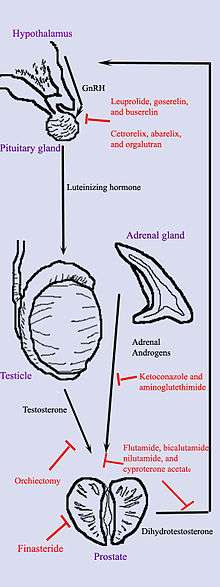

Hormonal therapy uses medications or surgery to block prostate cancer cells from getting dihydrotestosterone (DHT), a hormone produced in the prostate and required for the growth and spread of most prostate cancer cells. Blocking DHT often causes prostate cancer to stop growing and even shrink. However, hormonal therapy rarely cures prostate cancer because cancers that initially respond to hormonal therapy typically become resistant after one to two years. Hormonal therapy is, therefore, usually used when cancer has spread from the prostate. It may also be given to certain men undergoing radiation therapy or surgery to help prevent return of their cancer.[37]

Hormonal therapy for prostate cancer targets the pathways the body uses to produce DHT. A feedback loop involving the testicles, the hypothalamus, and the pituitary, adrenal, and prostate glands controls the blood levels of DHT. First, low blood levels of DHT stimulate the hypothalamus to produce gonadotropin-releasing hormone (GnRH). GnRH then stimulates the pituitary gland to produce luteinizing hormone (LH), and LH stimulates the testicles to produce testosterone. Finally, testosterone from the testicles and dehydroepiandrosterone from the adrenal glands stimulate the prostate to produce more DHT. Hormonal therapy can decrease levels of DHT by interrupting this pathway at any point. There are several forms of hormonal therapy:

- Orchiectomy, also called "castration," is surgery to remove the testicles. Because the testicles make most of the body's testosterone, after orchiectomy testosterone levels drop. Now the prostate not only lacks the testosterone stimulus to produce DHT but also does not have enough testosterone to transform into DHT. Orchiectomy is considered the gold standard of treatment.[38]

- Antiandrogens are medications such as flutamide, nilutamide, bicalutamide, enzalutamide, and cyproterone acetate that directly block the actions of testosterone and DHT within prostate cancer cells.

- Medications that block the production of adrenal androgens such as DHEA include ketoconazole and aminoglutethimide. Because the adrenal glands make only about 5% of the body's androgens, these medications are, in general, used only in combination with other methods that can block the 95% of androgens made by the testicles. These combined methods are called total androgen blockade (TAB). TAB can also be achieved using antiandrogens.

- GnRH action can be interrupted in one of two ways. GnRH antagonists such as abarelix and degarelix suppress the production of LH directly by acting on the anterior pituitary. GnRH agonists such as leuprolide and goserelin acetate suppress LH through the process of downregulation after an initial stimulation effect which can cause initial tumor flare. In order to prevent stimulation of tumor growth during the initial LH surge, an antiandrogen such as cyproterone acetate is prescribed a week before and three weeks after GnRH agonists are given. Abarelix and degarelix are examples of GnRH antagonists, whereas the GnRH agonists include leuprolide, goserelin, triptorelin, and buserelin. Initially, GnRH agonists increase the production of LH. However, because the constant supply of the medication does not match the body's natural production rhythm, production of both LH and GnRH decreases after a few weeks.[39]

The most successful hormonal treatments are orchiectomy and GnRH agonists. Despite their higher cost, GnRH agonists are often chosen over orchiectomy for cosmetic and emotional reasons. Eventually, total androgen blockade may prove to be better than orchiectomy or GnRH agonists used alone.

Each treatment has disadvantages that limit its use in certain circumstances. Although orchiectomy is a low-risk surgery, the psychological impact of removing the testicles can be significant, and sterility is certain. The loss of testosterone can cause hot flashes, weight gain, loss of libido, enlargement of the breasts (gynecomastia), impotence, penile atrophy, and osteoporosis. GnRH agonists eventually cause the same side effects as orchiectomy but may cause worse symptoms at the beginning of treatment. When GnRH agonists are first used, testosterone surges can lead to increased bone pain from metastatic cancer, so antiandrogens or abarelix is often added to blunt these side effects. Estrogens are not commonly used because they increase the risk for cardiovascular disease and blood clots. In general, the antiandrogens do not cause impotence, and usually cause less loss of bone and muscle mass. Ketoconazole can cause liver damage with prolonged use, and aminoglutethimide can cause skin rashes.